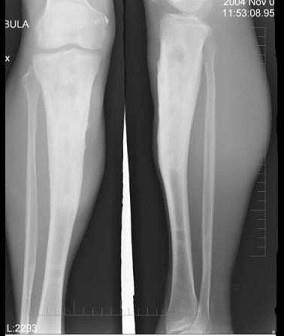

问题 47岁男性患者,右小腿反复肿胀,发热,摄片如图示,考虑为慢性化脓性骨髓炎,下列描述错误的是 ( )

选项 A、可见泥沙样死骨 B、以上都可见到 C、骨髓腔变窄,消失 D、骨质以增生硬化为主 E、骨干增粗,变形

答案 A